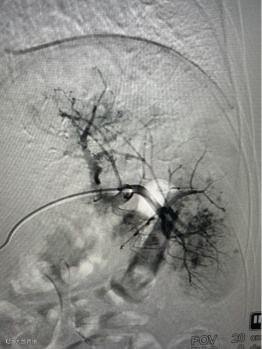

没有大开腹,没有全身麻醉。在患儿勇敢的配合下,手术仅在局部麻醉下进行。医生通过患儿大腿根部一个仅 “针眼”大小的穿刺点,将导管精准送入脾动脉。造影显示,患儿脾脏上下极均有广泛活动性出血,情况危急!

然而,血管外科介入团队沉着冷静,如同精准的导航,通过微导管超选择地将栓塞材料送至出血的血管。瞬间,造影显示活动性出血显著减少,被成功阻断!一场生命的危机,在几乎无创的条件下被化解。

造影脾动脉栓塞以远动脉显影减少,血流速度明显减慢,远端动脉分支造影剂外渗明显减少。